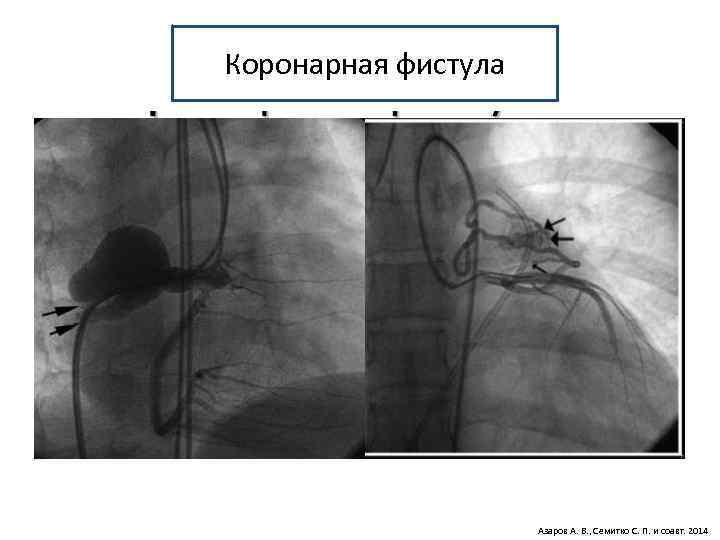

Аномалии коронарных артерий 1. Аномальное отхождение (Anomalies of the Origin). § Аномальное отхождение от лёгочной артерии (ACAPA). § Аномальное отхождение от аорты (ACAOS). § Единственная коронарная артерия (не отхождение) 2. Аномальное прохождение (Anomalies of the course). § Аномальное эпикардиальное. § Аномальное интрамуральное. § Удвоение артерии. 3. Аномальное окончание (Anomalies of termination). § Коронарная фистула. § Экстракардиальное кровоснабжение. 4. Комбинированные и сочетанные аномалии

Коронарная фистула Азаров А. В. , Семитко С. П. и соавт. 2014